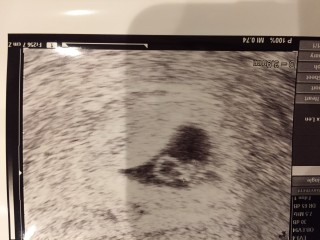

妊娠6週に入った頃に、まさかの階段から派手に転倒…。 おもいっきり尻もちをついて、お尻に大きなアザが!腕と足にもひどいアザができました。 真っ先にお腹の赤ちゃんが心配になり、病院で見てもらうと何の問題もなく順調とのことで安心しました(´;ω;`) 心臓もピコピコ動いているのが確認できて、なおさら安心(*^^*) 今はつわりで毎日の吐き気とだるさに加え、転倒のせいで腰はもちろん全身に痛みがあり、動くのも辛いためしんどい思いをしていますが…赤ちゃんも頑張って成長してくれてるので、お母さんも頑張って乗り越えなくては!と思っています!